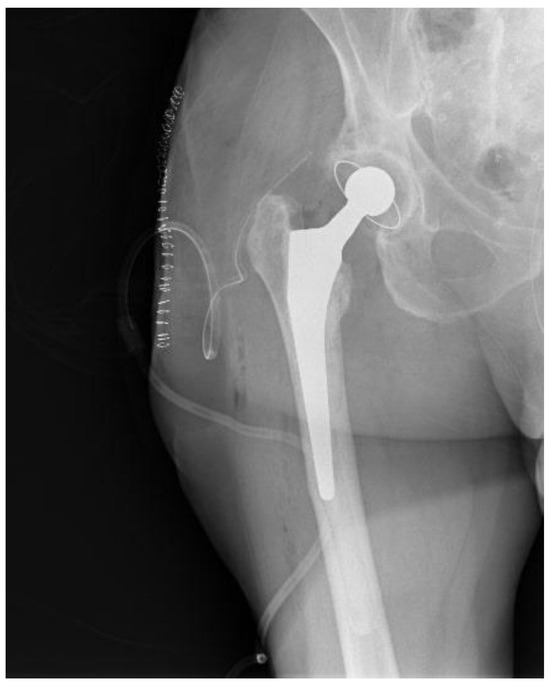

Regarding her orthopaedic medical history, four years previously, the patient underwent a right THA at a private institution through a standard Anterior Minimally Invasive Surgery (AMIS) approach (Figure 1). From the first postoperative days, serous wound drainage was discerned. Following that, she was reoperated on twice at the same hospital and by the same team, thirty days and forty-five days after the initial surgery, where wound exploration, debridement and washout with implant retention were performed due to residual pain and incessant wound leakage. Subsequently, the AMIS wound was not entirely healed, and the patient continued to complain about wound drainage and hip pain. She was discharged home with vacuum-assisted wound closure (VAC) and per os antibiotics. Finally, successful wound healing was achieved roughly four months after the primary THA.

Figure 1. Pelvis X-ray on admission date.